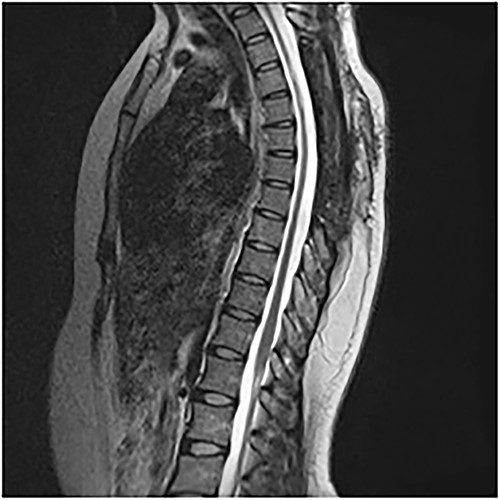

An MRI of the thoracolumbar spine was done, which showed an eccentrically located T4–7 cystic extradural mass causing severe cord compression. The spinal cord was flattened and displaced to the left (Figs 1 and 2).

On the first postoperative day, neurological examination revealed that power had returned to the preoperative state and her pain had significantly reduced. She was commenced on physiotherapy and on the third day postop, her limb pain had completely disappeared, while power had improved to 4 in the right lower extremity muscle groups. She was discharged on the fifth postoperative day and was to be seen in the out-patient clinic. Postop images showed total resection of cyst and gradual re-expansion of the spinal cord (Fig. 6). At 12-week follow-up, she had complete resolution of her preoperative symptoms and had returned to full functional independence.